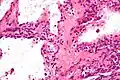

Pathologists classify serous cystic neoplasms into two broad groups. Those that are benign, that have not spread to other organs, are designated "serous cystadenoma".[5] Serous cystadenomas can be further sub-typed into microcystic, oligocystic (or macrocystic), solid, mixed serous-endocrine neoplasm, and VHL-associated serous cystic neoplasm. This latter classification scheme is useful because it highlights the range of appearances and the clinical associations of these neoplasms. Serous cystic neoplasms that have spread ("metastasized") to another organ are considered malignant and are designated "serous cystadenocarcinoma".

Pathology